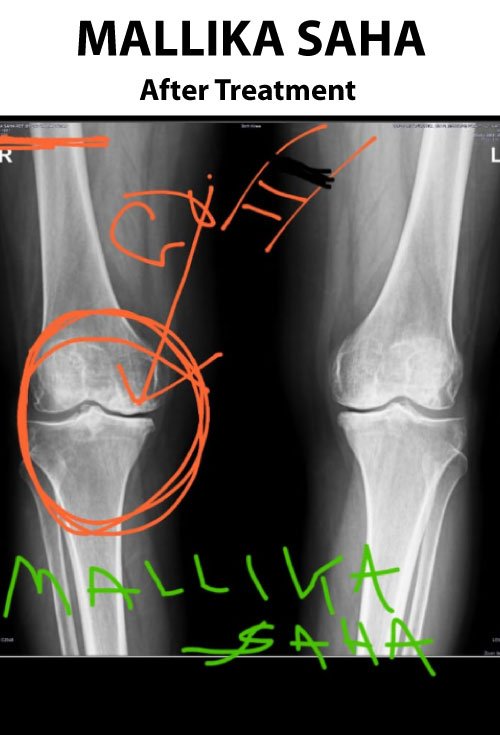

B. Goswami

I suffered from massive knee pain and difficulty walking. I had almost decided on knee replacement surgery, but after visiting Dr. N. Aman and taking 30 sittings of his special treatment, I realized surgery was not needed! Even after 6 months, I can still walk normally without problems.